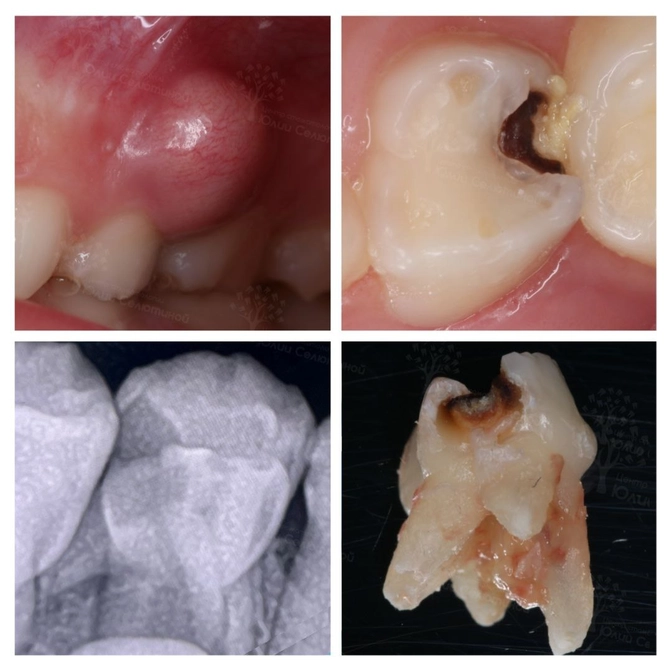

Вот с такой огромной шишкой на десне привели эту девочку в #ЦентрСелютиной.

Пациентке 8 лет.

«Четверка» молочная.

Разрушение началось на месте контакта с соседним зубом.

Вроде бы полость небольшая, а сам зуб чистенький-беленький.

Но огромнейший свищ — это прямое свидетельство воспаления внутри.

На снимке видим, что корень уже частично рассосался, а воспаление угрожает зачатку постоянного зуба.

Такой диагноз называется периодонтит — воспаление связочного аппарата, который удерживает зуб на месте.

Молочные зубы с таким диагнозом УДАЛЯЕМ❌